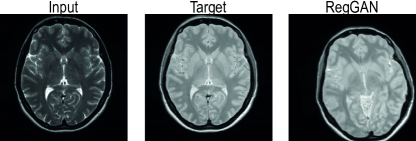

5.3.2 Semi-Synthetic Cross-Modality Brain MRI Synthesis

In recent years, a significant amount of research has emerged on applying deep learning to cross-modality brain MRI synthesis. Synthetically generated modalities have many possible down-stream use cases such as segmentation, classification, detection and diagnosis. [62]

We used brain images from Information eXtraction from Images (IXI) data set 444http://brain-development.org/ixi-data set/ to generate a semi-synthetic 3D data set for T2 to PD (proton density) synthesis, like in Wang et al. [59]. The main reason for choosing this task was that brain T2 and PD images are initially well aligned and hence provide good ground truths. Most of the images were already in resolution , the rest were also resampled to the same resolution. All the images were bias field corrected using N4 bias correction [53] with Advanced Normalization Tools (ANTs) software [5], and normalized based on brain white-matter using the implementation by Reinhold et al. [46] together with the implementation by Iglesias et al. [21] for brain mask extraction by dividing all image values such that the white-matter had mean value of one in each image. We used images for training, for validation, and for testing.

Results for the study on a validation set comparing different distributions of affine transformations for equivariance encouraging losses can be seen in Table 3. Based on the study we used combination of all four transformation types in the main experiment for which the results with a test set can be seen in Table 4.

All the three proposed variants of our method performed very well compared to the oracle model trained with aligned data and outperformed all the baselines with statistically significant margin on the voxel-wise metrics. NeMAR which also encourages deformation equivariance coupled with our 3D architecture is the only baseline trained on non-aligned data that came close to our method. RegGAN performed significantly worse and converged to produce severely misaligned predictions as visualized in Figure 8. Pix2pix model trained on the registered data set coupled with our 3D architecture also performed well but was still clearly behind our methods while surpassing all the other models trained on non-aligned data. CycleGAN was also unable to converge to a meaningful optimum due to the large misalignments. While rarely directly relevant in clinical context, our method also performed very well in terms of the FID score.